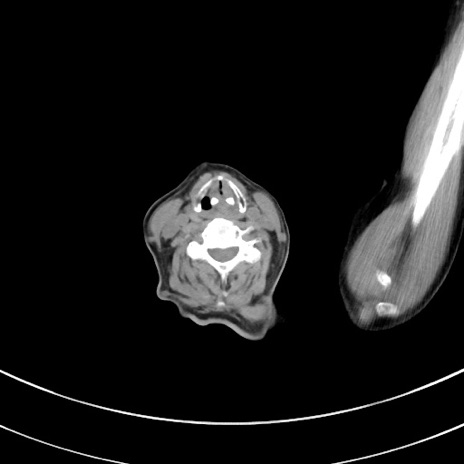

症例33(横断像)

【症例】70歳代 女性

【主訴】心窩部痛

【現病歴】延髄病変の精査・加療にて神経内科入院中。本日より心窩部痛あり。

【身体所見】右下腹部を中心に圧痛と反跳痛あり。